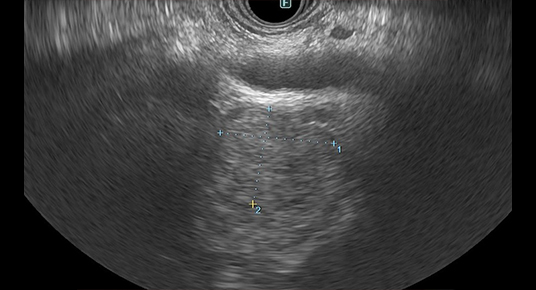

• 検査のイメージ

着色処理前

着色処理後